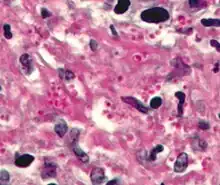

Haematoxylin and eosin staining is frequently used in histology to examine thin tissue sections.[10] Haematoxylin stains cell nuclei blue, while eosin stains cytoplasm, connective tissue and other extracellular substances pink or red.[10] Eosin is strongly absorbed by red blood cells, colouring them bright red. In a skillfully made H&E preparation the red blood cells are almost orange, and collagen and cytoplasm (especially muscle) acquire different shades of pink.